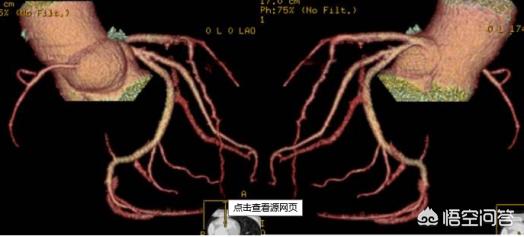

b. 心筋ブリッジ

このタイプはもっと不運だ。通常であれば冠動脈は心外膜の下の心筋の表面にあるが、「心筋ブリッジ」に罹患している人の場合、冠動脈が心筋の下に埋もれている部分があり、冠動脈の上を覆っている心筋を「心筋ブリッジ」と呼ぶ。冠動脈上の心筋橋の圧迫の程度によって、一般に安静時の心電図上では圧迫が軽度で無症状であるのに対し、40%以上の圧迫があると胸部圧迫感や胸痛、狭心症などの臨床症状が現れるとされている。下の図は、1心周期の間に心筋ブリッジによって冠動脈が圧迫される様子を示したもので、圧迫されると血管の全区間が細くなる。

それだけでなく、圧迫された冠動脈は、繰り返し圧力とねじれを受けるため、冠動脈攣縮を起こしやすくなる。また、血管の近位部では血液の乱れ(血液が血管内を十分にスムーズに流れない)などの血流障害があるため、冠動脈の動脈硬化(閉塞)が起こりやすくなり、その上、プラークの破裂、出血、血栓症、けいれんなどが起こり、急性冠症候群の発症につながる。この状況は本当に不運で、提案としてはやはり昔から言われているように、運動量、定期的な見直しである。今のところ、特に良い方法を聞いたことがないからだ。しかし、より多くの人がこの先天性異常を理解すれば、この状況は避けられる。